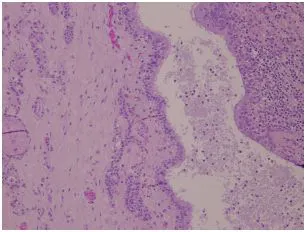

Fig. 3. Pared de un quiste tirogloso. Obsérvese la presencia de tejido tiroideo y, a la izquierda, el epitelio ciliado que tapiza la cavidad quística. (HE 10X)